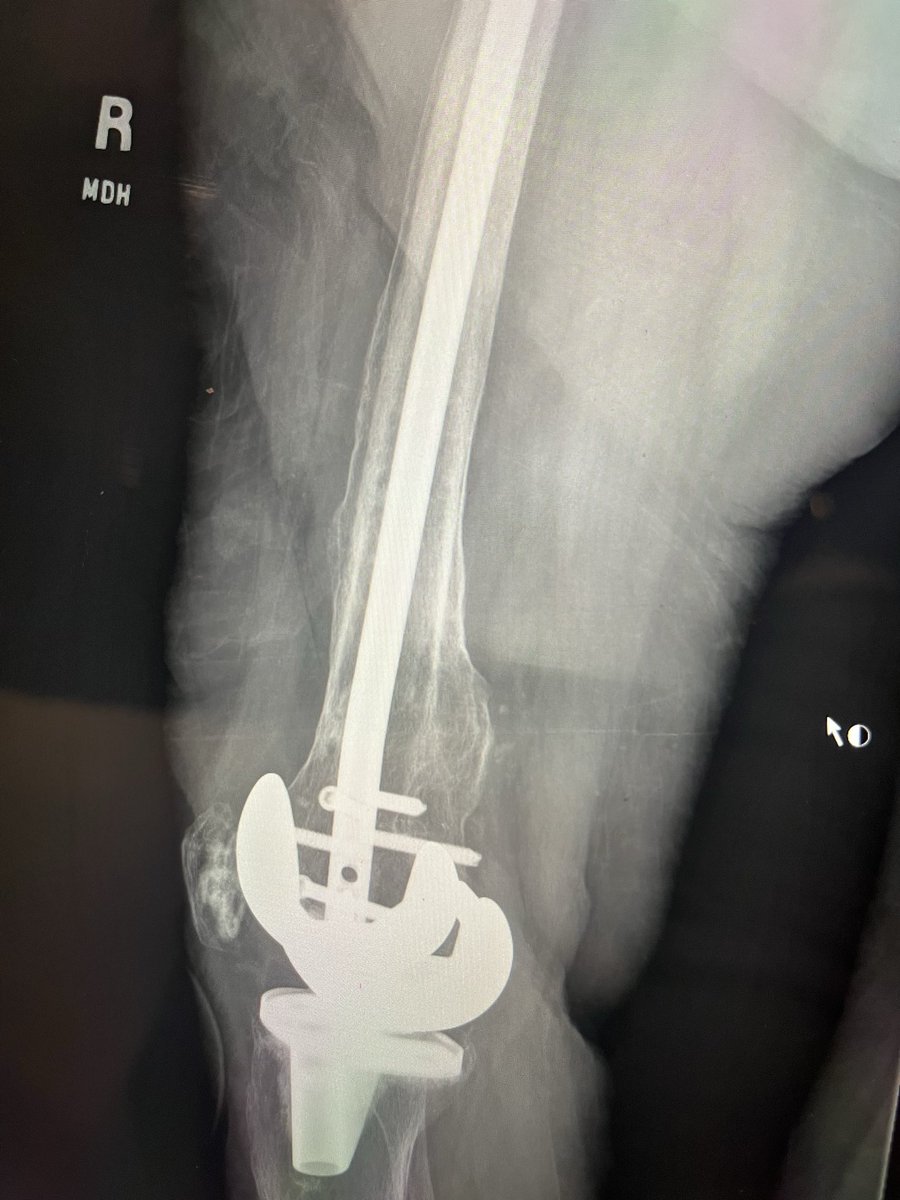

Can you answer our free question of the day? A patient presents to the trauma bay after involvement in a motor vehicle collision. Radiographs obtained in the trauma bay demonstrate a right distal femur fracture, as seen in Figure A. In surgery, the articular block is reduced, and reduction is held with headless compression screws. A retrograde intramedullary nail is then placed. After nail advancement, a varus and recurvatum deformity is noted at the fracture site with intraoperative fluoroscopy, as demonstrated via illustrations in Figures B and C. Placement of blocking screws in which locations (A - H) from Figure B and C would help correct this deformity? 1. B + E 2. A + G 3. B + F 4. C + H 5. D + H QID: 217509 Comment your answer below, then check to see if you got it correct by clicking the link below to see the answer & explanation. bit.ly/3OxP8sP #orthopedics #orthopedicsurgeon #orthopaedics #orthopaedic #orthopedic #ortholife #orthobullets #orthoresidents #orthoresident #orthoresidency #medicalschool #medicalstudent #medstudent #doctor